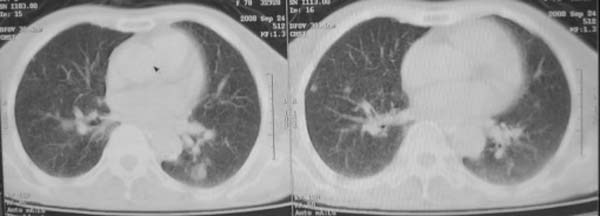

女,78岁,声嘶月余,否认有既往病史,有粉尘接触史10年。

肺癌伴纵膈、双颈部淋巴结转移;尘肺。

右上肺癌伴肺内转移及纵隔淋巴转移 左上肺结核 图像有点模糊

双上肺结节融合影,周围有纤维条索影,结合粉尘接触史,首先考虑尘肺。双侧颈部有增大淋巴结,有声嘶表现,肺癌淋巴结转移不能排除。可结合颈部淋巴结活检。